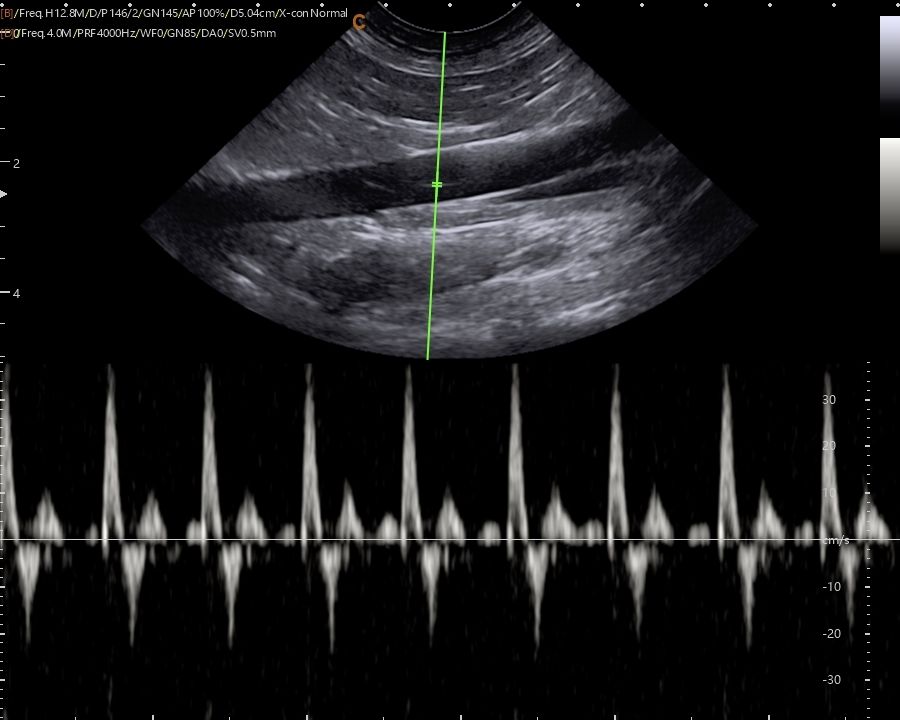

Images from the SonoBook 8 Vet